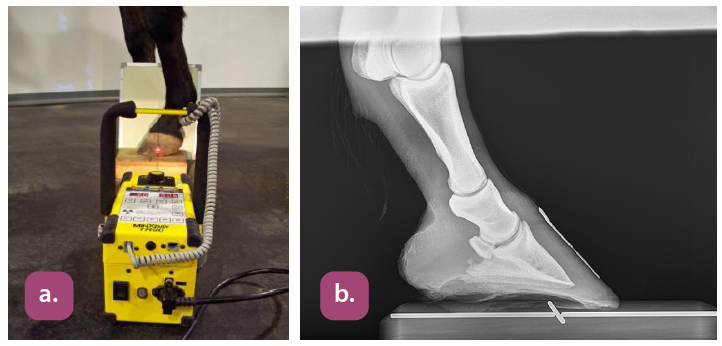

lateral coffin bone projection

45 degree dorsopalmar coffin bone projection

lateral navicular projection

skyline (palmar proximal) navicular projection